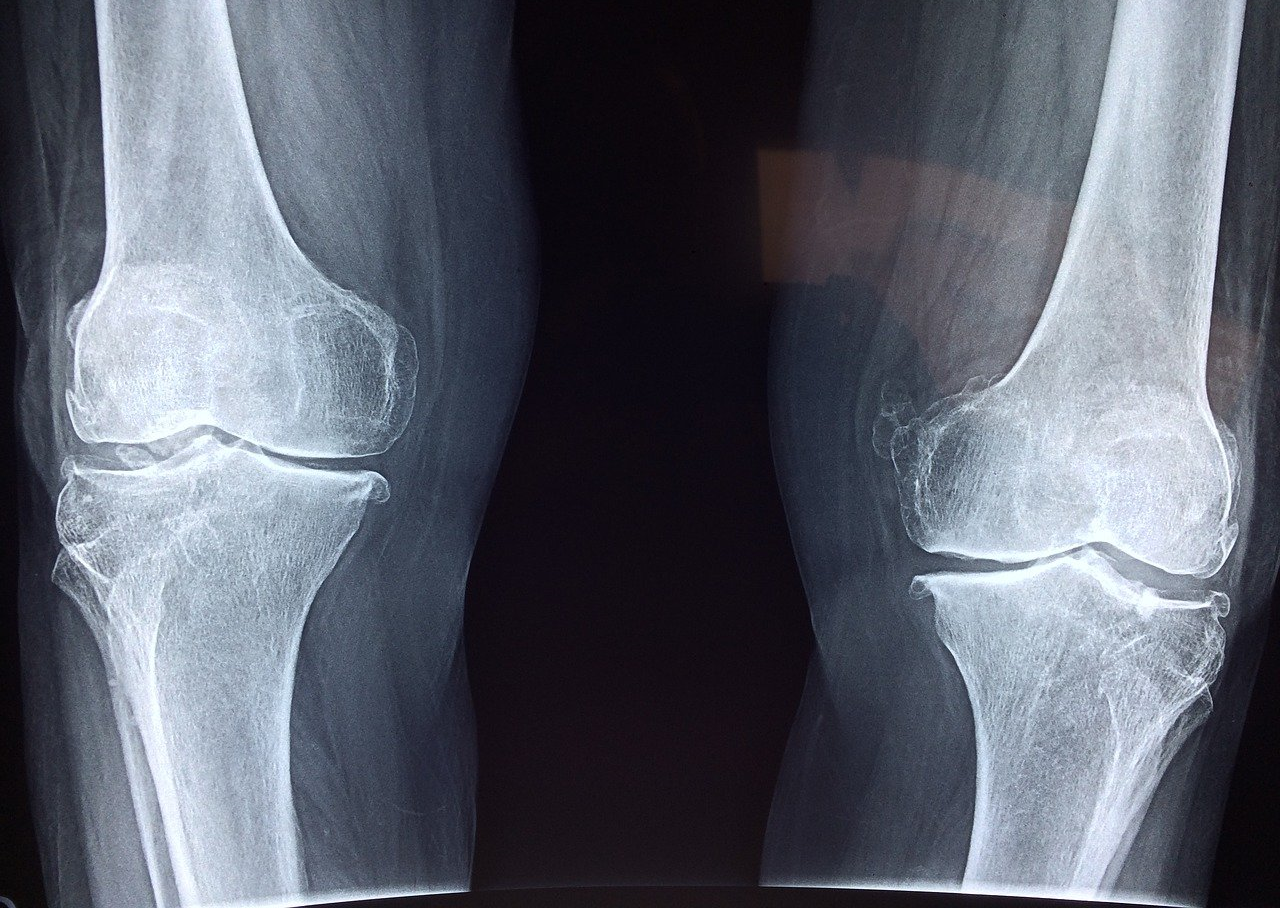

Orthopedics

Jagtap Superspeciality Hospital caters orthopedic care by performing all kinds of orthopedic surgeries. Our consultants available 24*7 to manage orthopedic emergencies.